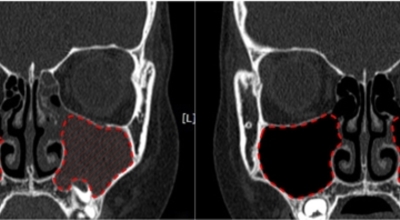

얼굴의 뼛속에는 몇 개의 빈 공간이 있습니다. 이러한 빈 공간을 '코 옆에 있는 동굴들'이라고 부르는 의미에서 부비동이라 해요. 이 공간은 머리 뼛속에 있는 뇌를 외부의 쇼크으로부터 보호해 주는 역할을 해요. 부비동염은 이러한 부비동이라는 빈 공간에 세균, 바이러스가 침투해서 염증이 발생한 질환을 의미해요. 부비동염은 흔히 '축농증'이라고 불립니다.

부비동염은 증상과 기간에 따라 '급성 부비동염'과 '만성 부비동염'으로 구분되어요. 부비동 코 주위의 얼굴 뼛속에 있는 빈 공간은 숨 쉬는 공기의 온도와 습도를 조절하며, 외부의 쇼크으로부터 뇌를 보호해요. 부비동은 작은 구멍을 통해 콧속과 연결됩니다. 이를 통해 콧속이 환기되고 부비동 내의 분비물이 자연스럽게 콧속으로 배출되어요. 부비동염은 이 부비동에 염증이 발생해서 콧물이 배출되지 못하고 고여 있는 상태를 말해요.

내과적 치료에 반응하지 않는 만성 부비동염의 경우 수술 치료가 필요해요. 첫째, 자연공을 통한 부비동의 배액과 환기 유지입니다. 둘째, 발병의 선행 요인인 비강 내 구조적 이상을 제거하던가 교정하는 것으로 보입니다. 셋째, 부비동 점막의 병변이 비가역적이라면, 부비동 점막을 제거하는 것으로 보입니다. 보통은 부비동 내시경 수술을 시행해요.